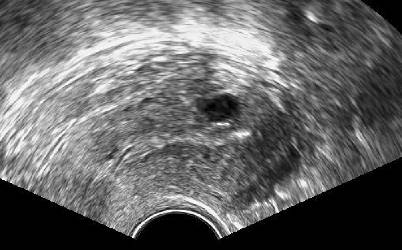

Abb. 3

Zystische Strukturen im Myometrium, die einzeln oder in Gruppen vorkommen können, finden sich bei Adenomyose